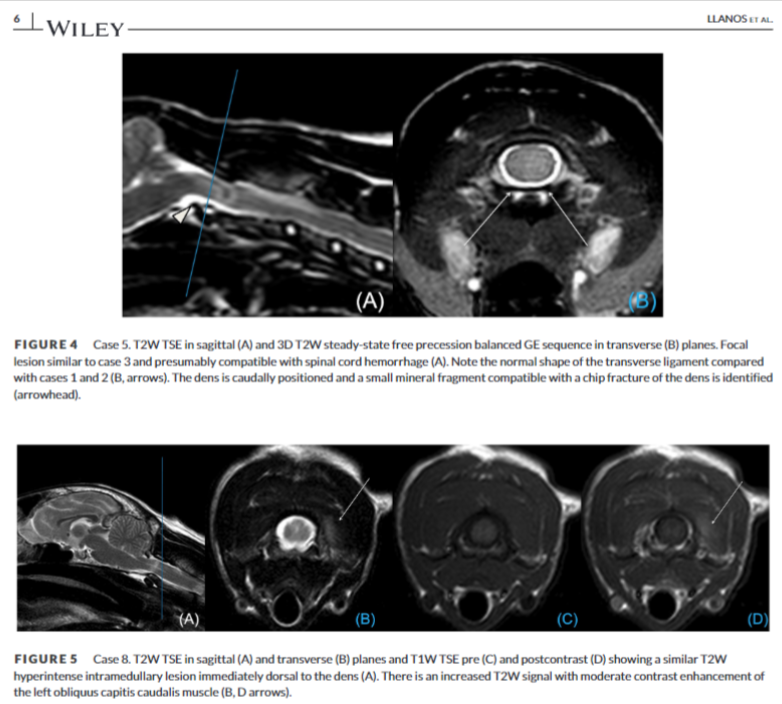

'traumatic atlantoaxial hyperflexion'은 고양이에서 발생하는 희귀한 질환으로, 머리 외상이나 교통사고와 같은 외상성 사건 이후에 발생하는 급성 신경학적 징후를 특징으로 한다. 이는 환축추 관절(고양이의 첫 번째 및 두 번째 목뼈 사이의 관절)의 과도한 굴곡으로 인해 발생하며, 결과적으로 척수 압박 및 손상을 초래한다.

통상 이야기 하는 개에서의 AAI(atlantoaxial instability)의 설명과 동일하지만 AAI의 경우 유전소인과 기형 등도 포함되기 때문에 고양이에서는 AAI라는 용어보다 hyperflexion로 사용한다.

외상성 환축추 과굴곡증은 외상 후 급성 C1-C5 척수병증을 보이는 고양이에서 중요한 감별 진단이며, MRI는 이 질환을 ANNPE(acute noncompressive nucleus pulposus extrusion), 허혈성 척수병증 또는 척추 골절과 같은 다른 급성 경부 척수병증과 구별하는 데 매우 중요하다. 개의 AAI의 경우 너무 흔하여 통상 MRI 검사를 잘하지 않으나 고양이에서는 드물기 때문에 MRI 검사가 필수적이라는 의미로 사용될 수 있다.